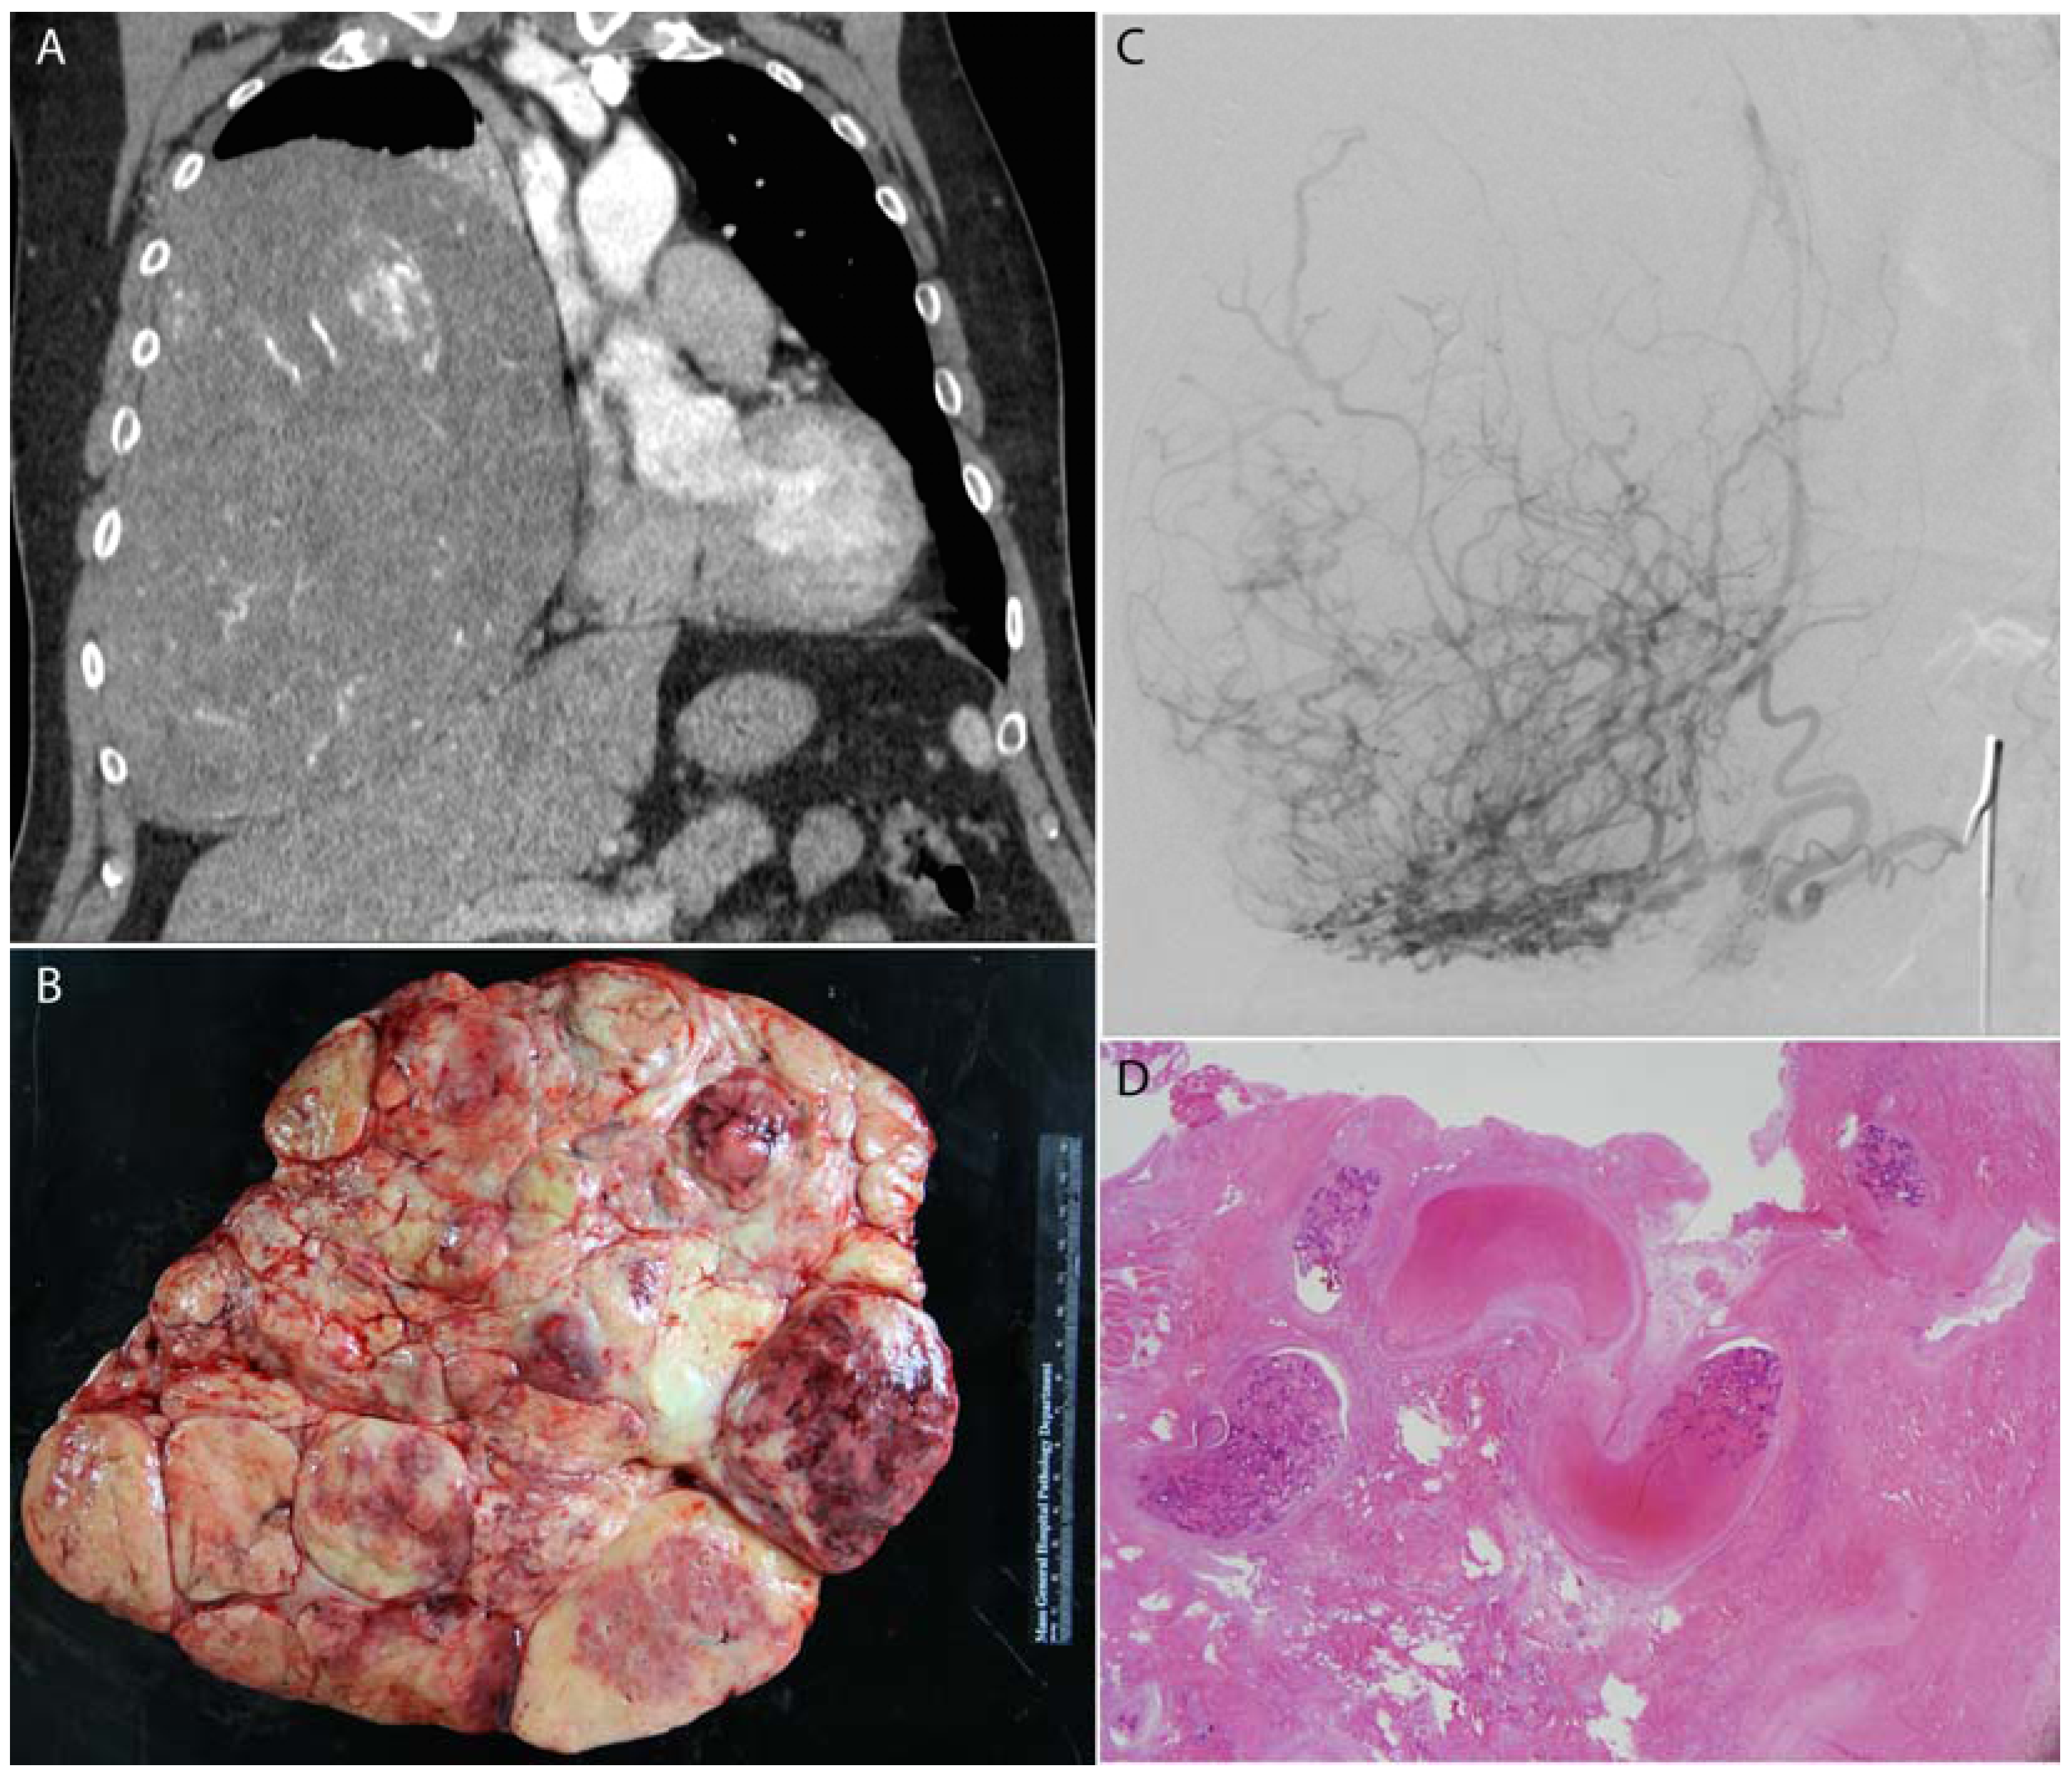

Figure 1.

A large benign solitary fibrous tumor of the right pleura (A) was pre-operatively embolized with Gelfoam; (B) surgical resection photograph; (C) angiography of the right phrenic artery demonstrated exuberant vascularity within the mass; (D) histology demonstrates fragments of Gelfoam (acellular pink material) within blood vessels in the mass which is entirely infarcted.